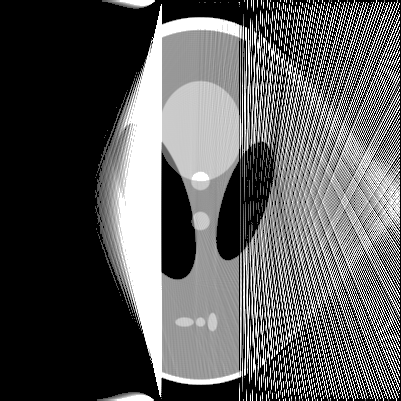

The proposed method was performed for various computer-simulated data, including perfect, noisy, non-truncated and truncated data. Figure 2 displays the reconstructed images from perfect data, while figure 3 displays the reconstruction from noised data for and . The images in top row are reconstructed from non-truncated projection data, while these in the bottom row are reconstructed from the truncated data such that any measurement corresponding to a line not passing through the rectangular box in figure 1(a) was discarded.

From figures 2 and 3, we can see that the presented algorithms can carry out the reconstruction of SPECT efficiently. As our expectation, the distortions in the reconstructions raise with the increase of the attenuation coefficient . The profiles of the reconstructions in figure 2 at are displayed in figure 4. Similar to [1], we have the same observation that the noise in the reconstructions appears strongly spatial variant, for which the reason is the weight variant in (3)(see [1] for details).